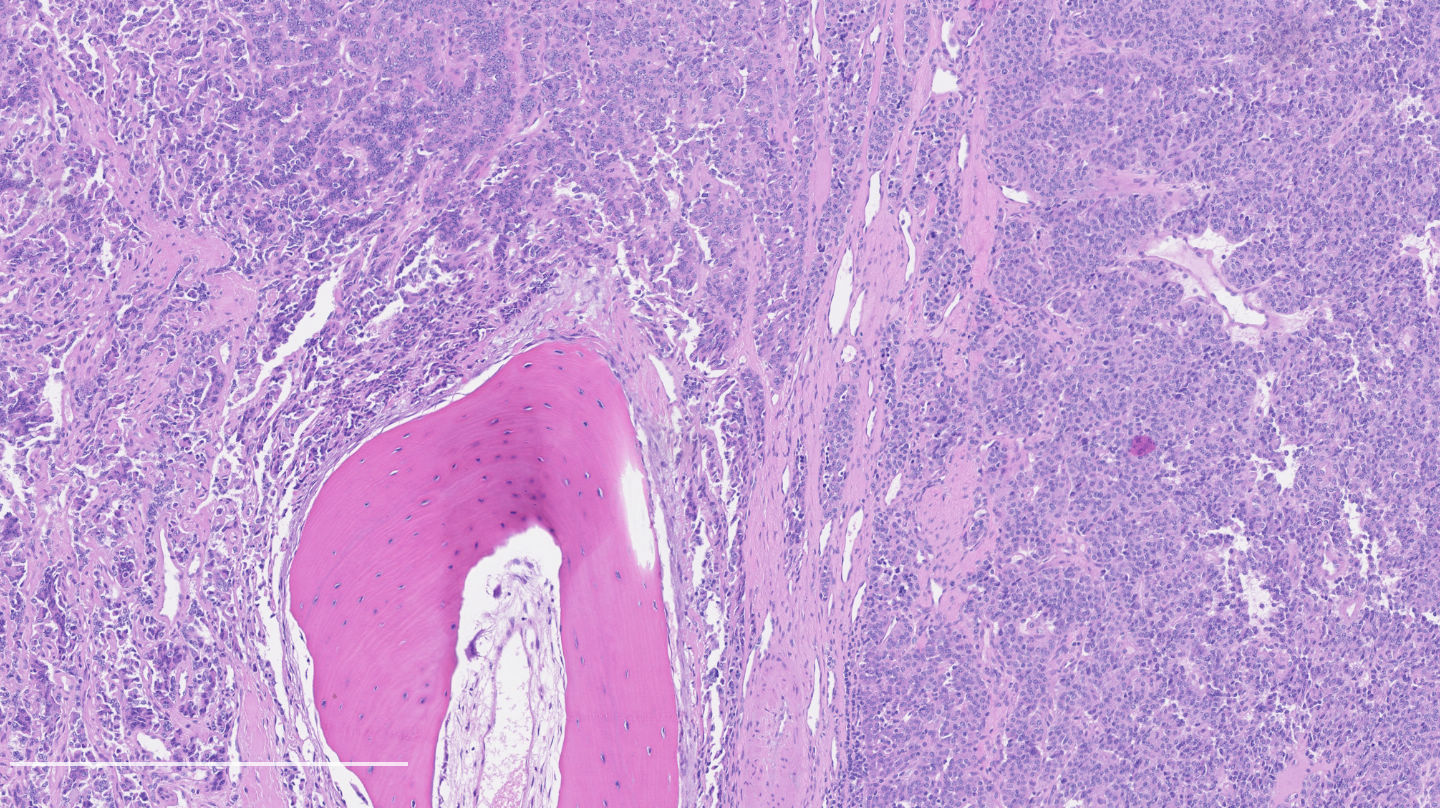

Contributed by Philippe Joubert, M.D., Ph.D.

- A patient undergoes a lobectomy for a well circumscribed nodule. On H&E slide, the tumor exhibits a well differentiated neuroendocrine morphology and you observe the histologic features presented in the image. Which of the following statements is true?

B. It is defined as a well differentiated neuroendocrine tumor with 2 - 10 mitoses per 2 mm² or foci of necrosis. The picture shows a carcinoid lung tumor with a classical neuroendocrine morphology and 2 mitoses in 1 high power field. Even though the whole tumor is not presented here, the presence of 2 mitoses is sufficient for an atypical carcinoid diagnosis.

While Ki67 proliferation rate is frequently > 10% in atypical carcinoids, this feature is not part of the diagnosis (A). C is nearly exact but mitotic count is not made on 1 high power field. Finally, the diagnosis can be suggested on small samples but a thorough examination of a resection specimen is necessary to confirm an atypical carcinoid diagnosis (D).